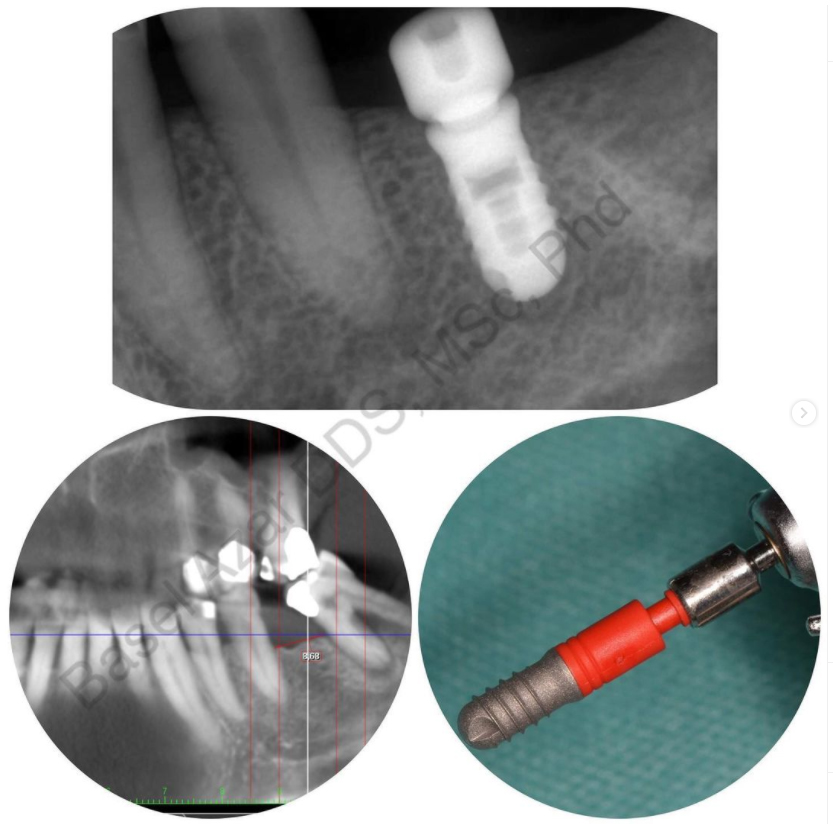

Implantaty